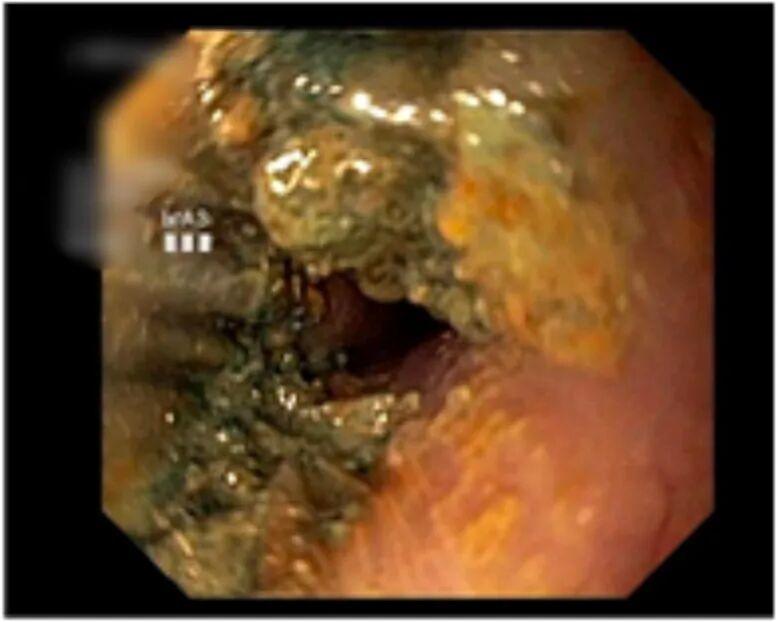

术前检查刚一完成,医师便迅速开展胃镜手术,此时画面让人揪心:纽扣电池已牢牢嵌顿在食管处,周围黏膜不仅明显水肿,还出现了黑焦样的腐蚀痕迹。

这枚“滚刀肉”般的纽扣电池取出难度极大,医师凭借精准操作,终于用异物钳将其成功取出。若再晚一步,可能导致食管穿孔、大出血,甚至危及生命。